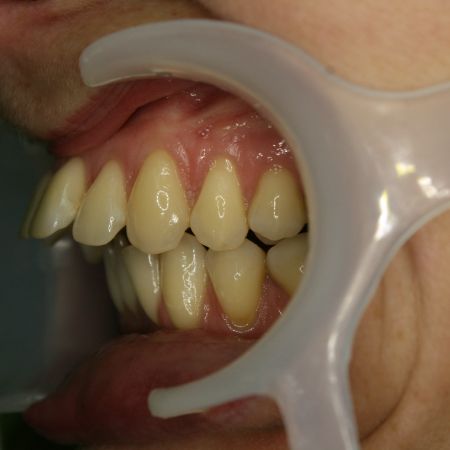

Vor der Behandlung

Bei dieser Patientin standen die oberen Schneidezähne so weit vor, daß sie auf der Unterlippe aufstanden, und der Mund nicht richtig geschlossen werden konnte. Zu der Fehlstellung trugen sowohl die stark nach vorne gekippten oberen Schneidezähne, als auch der zu kurze, zurückliegende Unterkiefer bei. Die Patientin litt sehr unter ihrer Fehlstellung, hatte aber zu große Bedenken, sich den Unterkiefer chirurgisch nach vorne setzen zu lassen. Um obere und untere Schneidezähne dennoch in Kontakt zu bringen, wurden im Oberkiefer zwei kleine Backenzähne entfernt. Die entstandenen Lücken wurden dazu genutzt, die oberen Frontzähne zurückzuziehen. Dabei mußte besonderes Augenmerk auf die folgenden Punkte gerichtet werden: